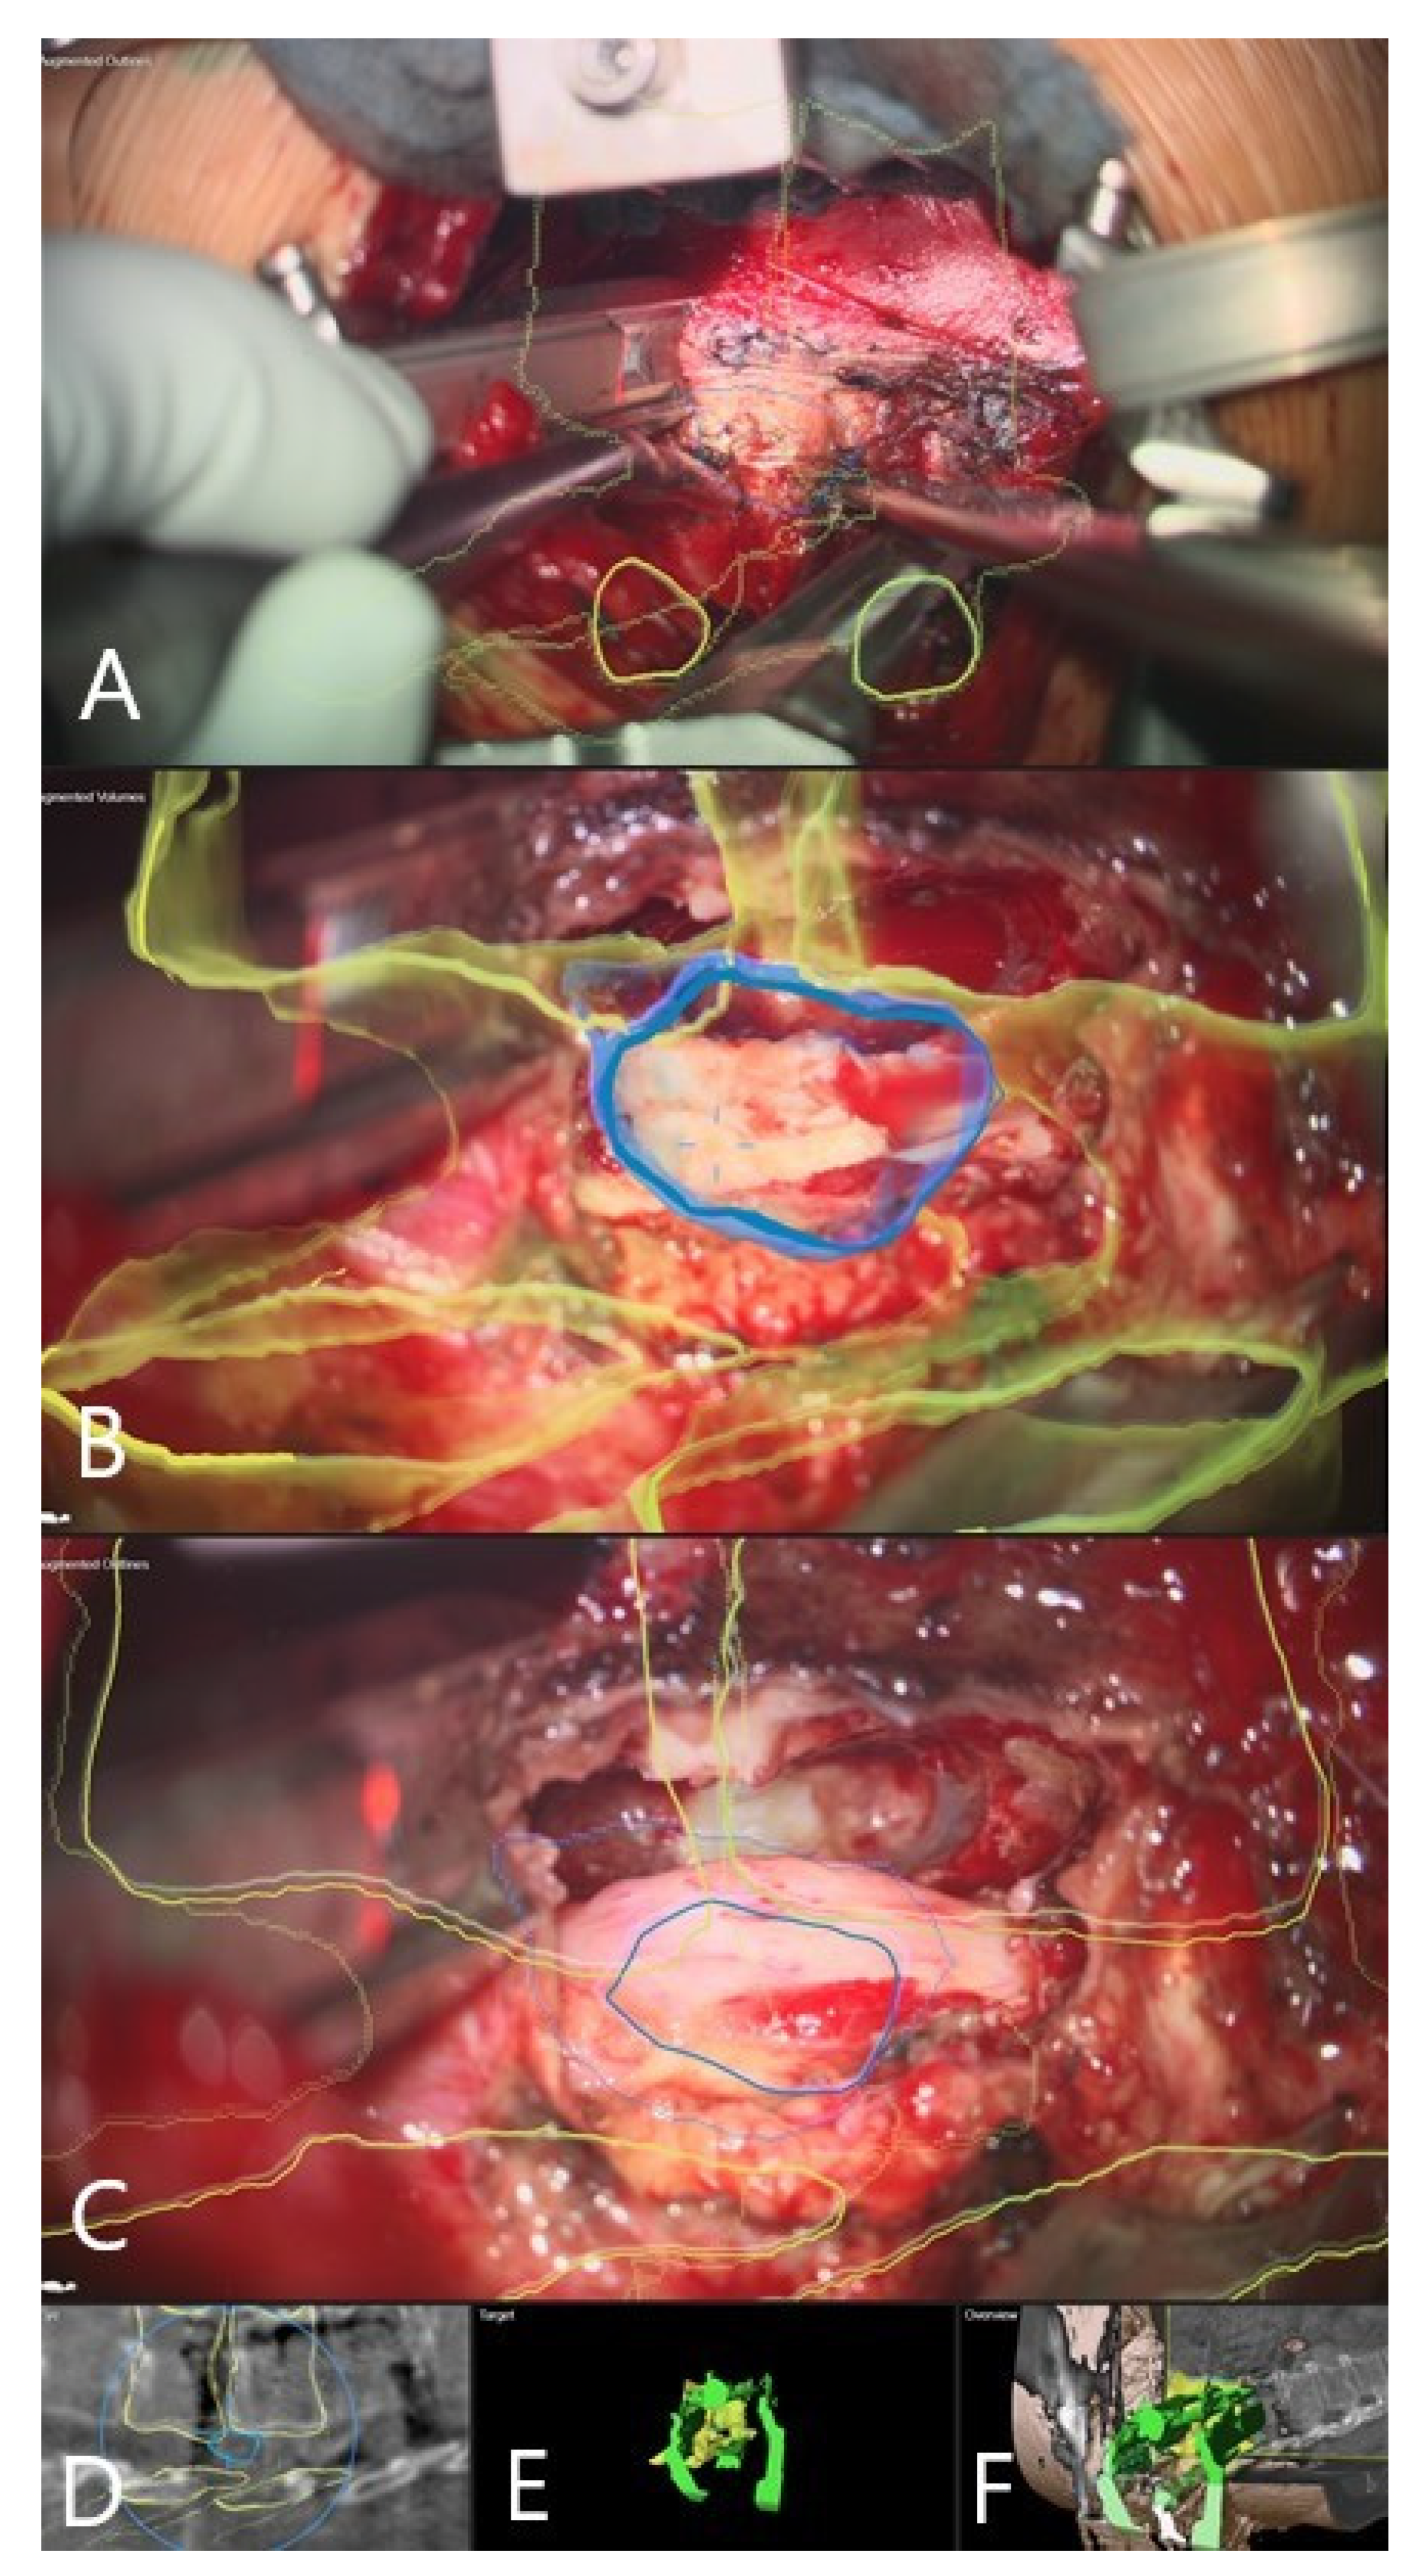

3.4. Augmented Reality

3.5. Clinical Application of iCT and AR